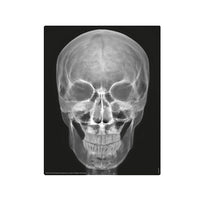

Build a full human skeleton set, complete as glow magnets. Learn how the skeleton supports our body. Includes “magic” x-ray films that let you “see through” the human body!